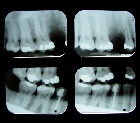

Cuando los niños pequeños son propensos a la caries dental, podrían perder los dientes de leche mucho antes de lo que deberían. También pueden sentir un cierto grado de incomodidad cuando se desarrollan en las cavidades profundas que empiezan a afectar a los nervios por encima de las raíces de los dientes y en estos casos es recomendado una pulpotomía.